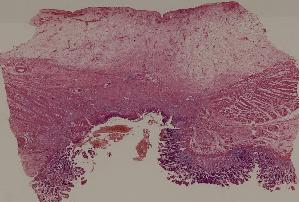

60.胃溃疡

低倍视野